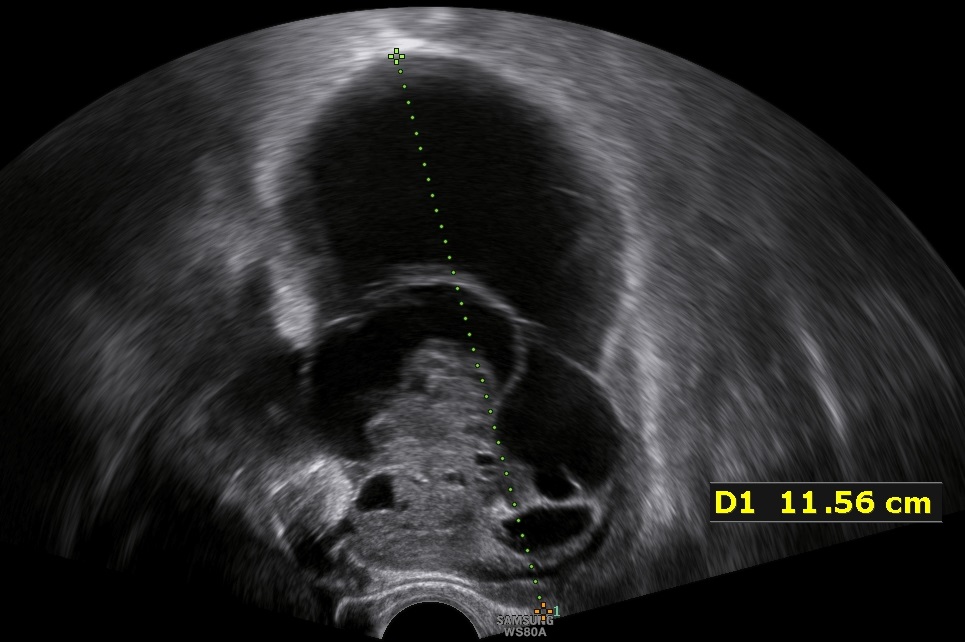

- 31-year old P1 with unilateral, 11.5cm large, multilocular, cystic ovarian tumor with solid components up to 4.2cm cointaining feeding vessels in doppler-sonography. CA-125 was negative. The patient desired further future pregnancies.